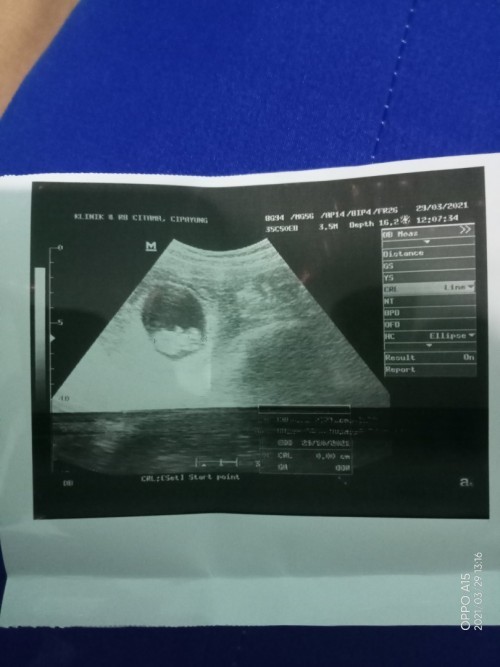

wajar. ini usg ku uk 8w.